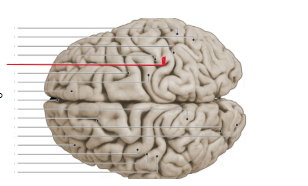

lobus frontalis

lobus parietalis

lobus occipitalis

lobus temporalis

gyrus precentralis

gyrus postcentralis

sulcus centralis

sulcus lateralis

sulcus cinguli

fissura longitudinalis cerebri